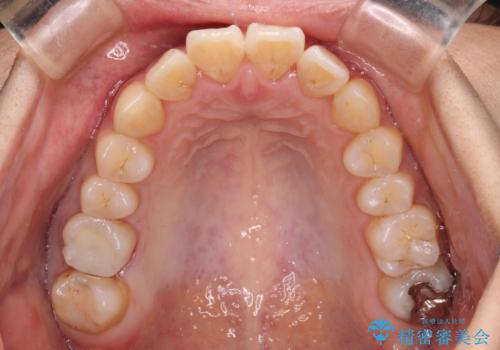

- 前方に傾斜した上下の前歯を気にして来院された患者様です。

唇の閉じにくさや横顔のシルエットが気になるような突出感ではなかったため、インビザラインを用いて、歯列の遠心移動とIPR(歯と歯の間を削る)により前歯の傾斜を改善していくこととしました。